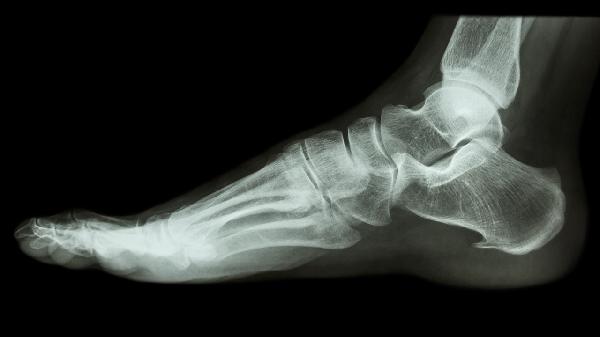

跟骨承重功能特殊,未完全愈合时过早行走可能导致骨痂微损伤。肿胀常伴随负重后疼痛加剧。需通过X线确认愈合程度,必要时延长制动期,使用步行靴分散压力。